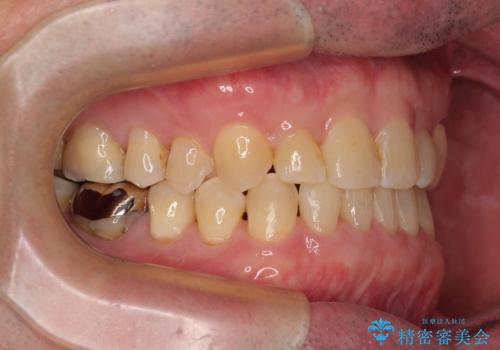

- 上下前歯の反対咬合と左下奥歯の痛みを気にして来院された患者様です。

歯並びや口元の印象、奥歯の咬み合わせから、非抜歯にて矯正治療を行うこととしました。

また、左下の奥歯は親知らずの影響で手前の歯の歯根までむし歯になってしまったため、親知らずとともに抜歯をし、インプラントによる補綴治療を行うこととしました。

インプラント埋入による仮歯の装着や、前歯の反対咬合の改善は比較的スムーズに達成されましたが、舌突出癖などの影響による、歯列全体のスペースを閉じることが難航し、期間がかかってしまいました。